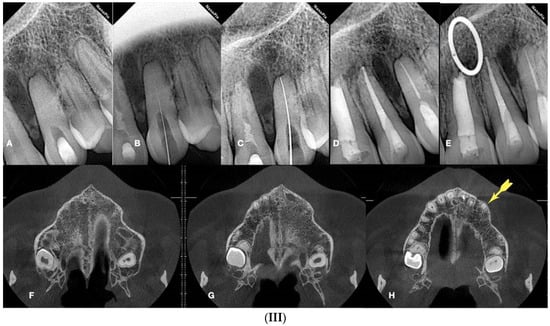

(I) (A) Preoperative panorax focused on the impacted right maxillary canine, revealing a large lesion. (B) Two-year follow-up panorax after the surgical removal of the lesion revealing healing. (C,D) Periapical radiographs reveal recurrent disease 6 years after the surgical intervention. Notice that the maxillary canine was brought in occlusion with orthodontic treatment, but the canal was rendered radiographically blocked. (E,F) CBCT axial slices evaluate the magnitude of the periapical lesion and the root canal calcification of the maxillary canine. (II) (A,B) Clinical microscopic image from two different angles of the previously initiated access cavities. Notice the gray spot indicating the calcified root canal orifice (yellow arrow). (C) Clinical image of the initial troughing of the calcified canal with a round long shafted bur (Munce bur). (D) EDM file during the buckling resistance activation test negotiation technique. (E) Clinical image of the calcified orifice after the first BRAT stroke. Canal negotiation with the 08 D-finder file is now possible. (III) A Preoperative periapical radiograph. (B) Periapical radiograph demonstrating the initial negotiation of an 08 D-finder after the first BRAT stroke. (C) Periapical length determination radiograph. (D) Postoperative radiograph. (E) One-year follow-up periapical radiograph. (F–H) Three-year follow-up cbct reveals complete healing of the periapical lesion (axial slices) (clinical images and radiographs courtesy of Dr. Chaniotis Antonis). Red arrows indicate the calcified canal location, and Yellow arrows indicate the impacted canine. The white circle is the projection of a nose piercing ring in the radiograph (not a symbol).